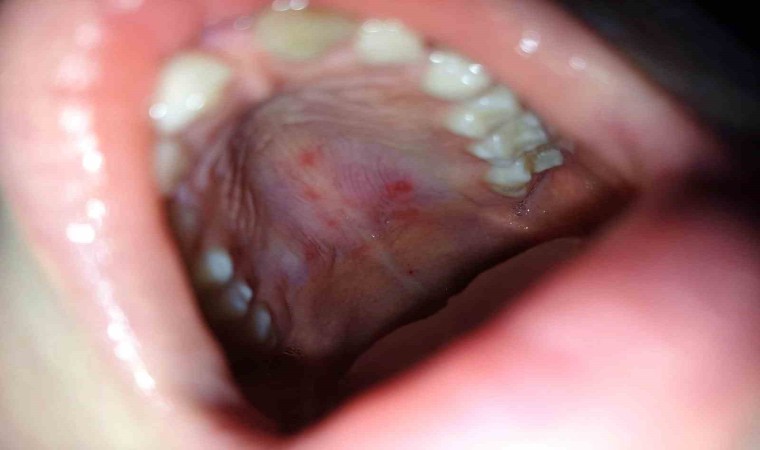

Hastalığın belirtileri ve dikkat edilmesi gereken hususlardan bahseden Medicana International Samsun Hastanesi Çocuk Sağlığı ve Hastalıkları Uzmanı Dr. Mustafa Alper Aykanat, “Ateş, boğaz ağrısı, dil, diş etleri ve yanakların iç kısmında kabarcık şeklinde lezyonlar, avuç içi ve ayak tabanlarında döküntü, bebek ve küçük çocuklarda huzursuzluk, iştah kaybı ve yutma zorluğu şeklinde belirtileri vardır. El-ayak-ağız hastalığı, küçük RNA virüsleri olan döküntülü bir hastalıktır. Hastalık damlacık yoluyla bulaşır bu nedenle okul ya da kreşteki çocuklar arasında bulaşması kolay olur. El- ayak-ağız hastalığı şüphesi olan çocuklarda pediatri hekimi çocuğun bilgilerini aileden aldıktan sonra fiziki muayeneyi yaparak tanısını koyar. Laboratuvar tetkikleriyle de desteklenir. El-ayak-ağız hastalığı tedavisi için özel bir uygulama yoktur. Bu hastalığının belirtileri genellikle 7 ila 10 gün içinde düzelir. Ağız yaralarının ağrısını hafifletmek için topikal oral anestezikler, çeşitli ağrı kesici ateş düşürücüler semptomları azaltmak için kullanılmaktadır. Hastalık döneminde sıvı tüketiminin artırılması, liften zengin, probiyotik içerikli gıdalarla beslenilmesi iyileşme açısından önemlidir. Ayrıca çocuk hastalık süresince dinlendirilmelidir” dedi.